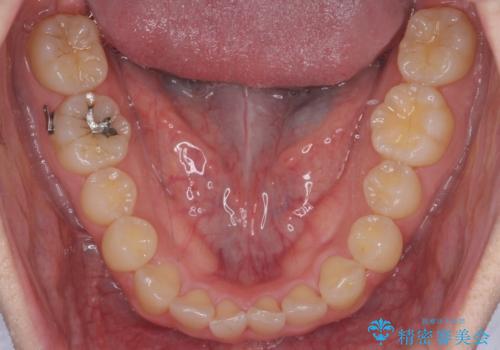

引っ込んだ前歯を並べる 歯を抜かないマウスピース矯正

- 右上の前歯が内側に入っているのを気にして来院。

右上の奥歯を後ろに移動して、前に出すスペースを確保してから並べました。

奥歯を後ろに送るために、矯正用インプラントを使用しています。

口を開けたとき、笑顔の印象が大きく変わり、大変喜んでいただけました。